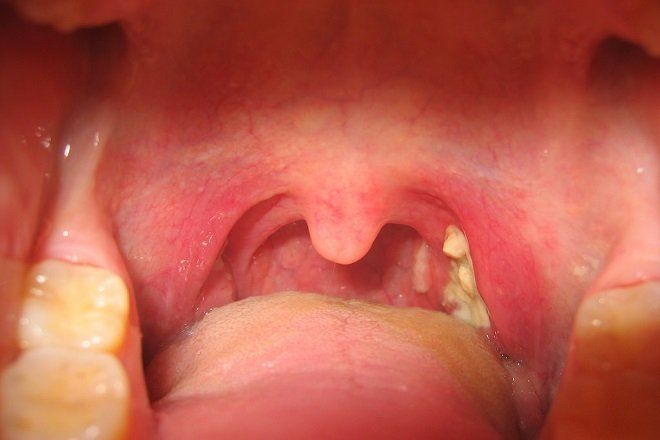

3. Triệu chứng của viêm họng cấp

Triệu chứng thường gặp nhất của viêm họng cấp là đau rát họng, khô họng và ngứa họng. Ngoài các triệu chứng tại chỗ này, bệnh nhân có thể có biểu hiện toàn thân như sốt, mệt mỏi, chán ăn, ... Tùy thuộc vào nguyên nhân, các triệu chứng của viêm họng cấp có thể thay đổi:

Các triệu chứng của viêm họng cấp do virus bao gồm:

Các triệu chứng viêm họng cấp do vi khuẩn bao gồm:

- Nuốt rất đau

- Sưng các hạch vùng cổ

- Thấy các mảng màu trắng ở trong họng khi soi qua gương hoặc đèn pin.

- Amydan 2 bên sung đỏ.